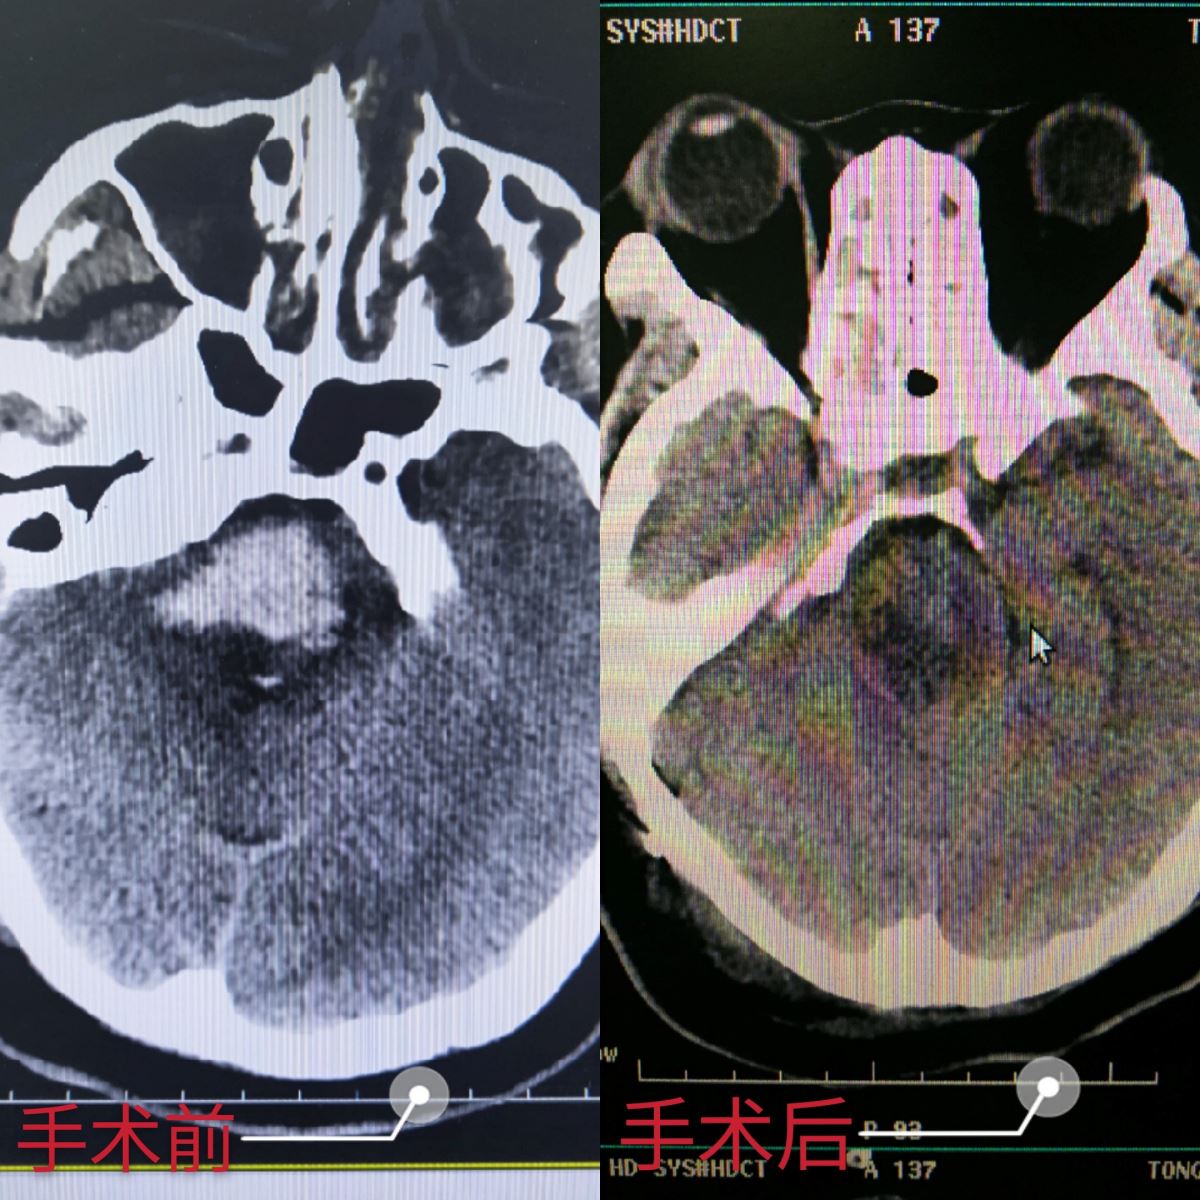

患者女性,38岁,为一名医务工作者,在值班期间突然发病,因恶心、呕吐、头痛伴意识模糊,入住我院急诊EICU,初步诊断为脑干出血。因患者病情较重,入院两天后复查CT,脑干出血明显增多,一般脑出血患者出血量5ml的致死率为90%,该患者的出血量已接近15ml,严重危及生命。我院神经外科赵林副主任医师会诊后建议马上进行手术治疗,经赵林医生耐心细致地与患者家属沟通,面对唯一的生机,患者家属决定放手一搏。手术由天坛医院李俊杰主任医师及赵林医生共同完成,顺利为患者在全麻下进行右侧枕下乙状窦后入路脑干血肿清除术,经过3个多小时的手术,成功为患者清除血肿。尽管手术难度较大,但赵林医生凭借自己丰富的临床经验,精准定位,进入血肿腔,在保护好脑干的前提下,顺利为患者清除血肿,将患者从死亡线上拉了回来。术后,患者进入ICU观察治疗。经过一周的治疗和恢复,目前患者可自主眨眼,有咳痰反应,已脱离呼吸机恢复自主呼吸,病人情况正在逐渐好转。

脑干出血是脑出血疾病中危险程度最高的急症,致死率高达80%以上。脑干被称之为神经外科手术的禁区,此次手术的成功开展标志着我院神经外科治疗脑出血手术技术迈上了新台阶。近年来,我院神经外科团队积极探索、大胆创新,积极开展颅脑肿瘤、脑干出血探索性手术,技术水平不断提高,让众多患者得以重生,赢得百姓广泛赞誉。